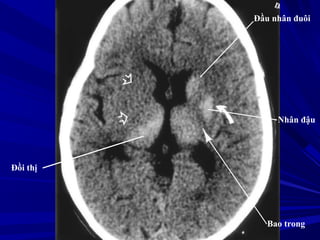

Nhân đậu

Bao trong

Đầu nhân đuôi

Đồi thị

Cánh tay sau